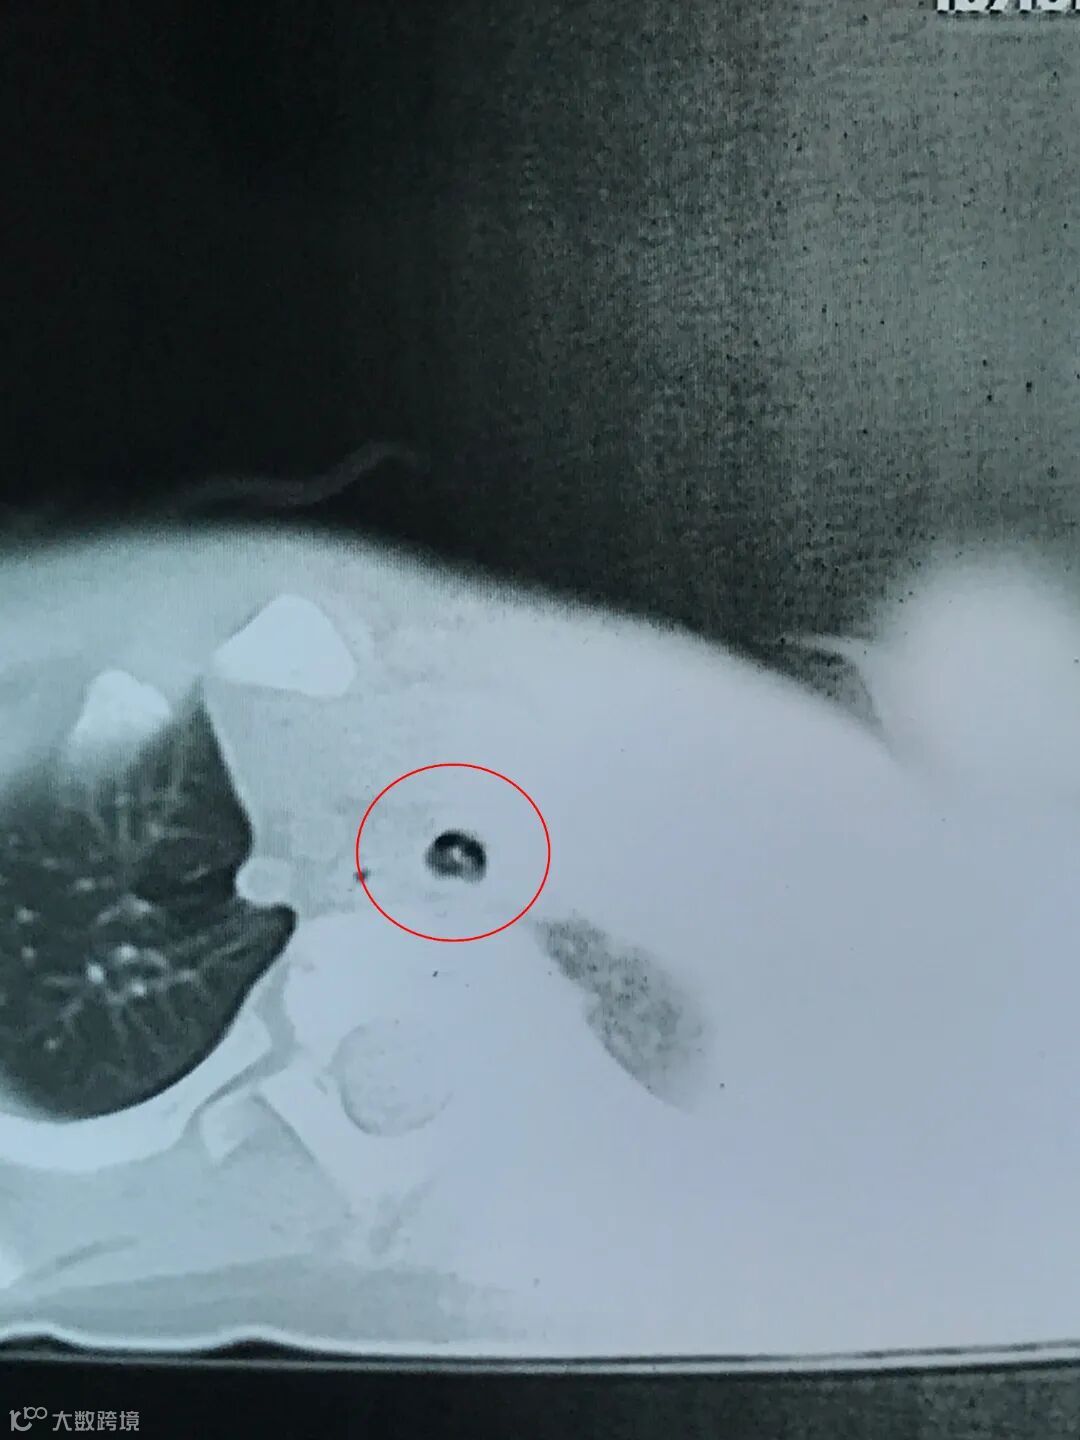

26日下午16时,患儿收入市人民医院儿科住院,气管异物病因非常明确,需要及时手术取出异物,以防后患。当天休息的儿科副主任医师潘光婷得知情况后立即从家里赶往医院。

医生和家长充分沟通手术方案和可能发生的风险,一岁多大的患儿气管非常狭小,一旦操作不慎,鱼骨划破血管导致大出血便有窒息的风险。家长此时又有些犹豫,中途咨询医生亲戚,考虑是否转去上级医院治疗会否更好,经过深思熟虑后最终决定留在北海治疗。